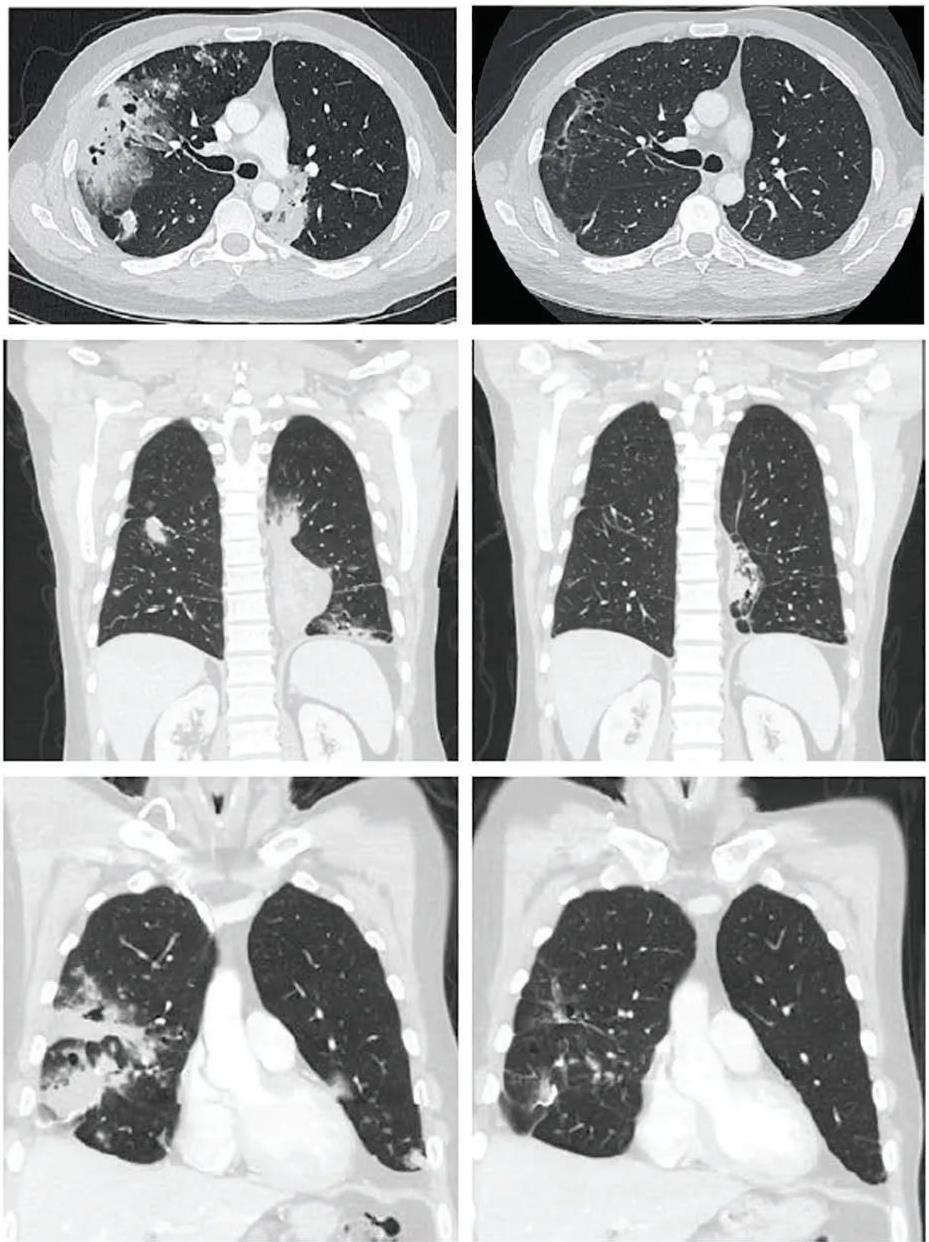

值得一提的是,其中一位男性IV期肺黏液腺癌患者,复查CT显示,在TIL治疗前、TIL治疗6周后,反应持续时间为1.1+~26.2+个月。在TIL治疗后12周,获得81%的部分缓解(PR)(详见下图)。

▲图源“Cancer Discov”,版权归原作者所有,如无意中侵犯了知识产权,请联系我们删除